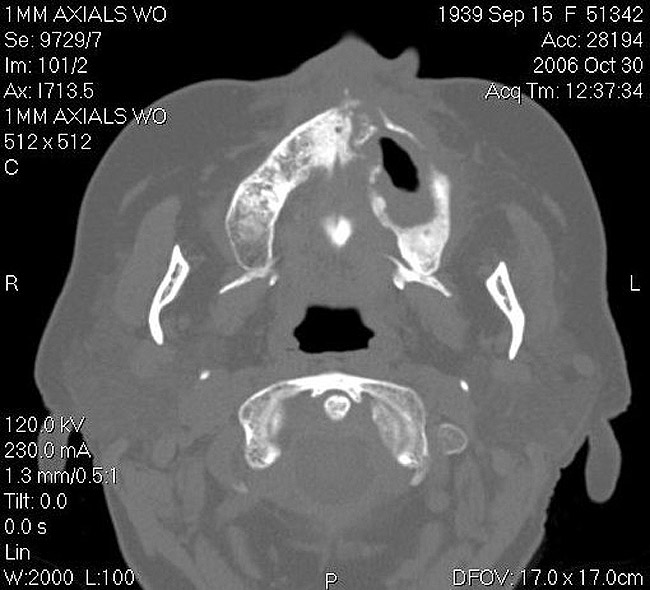

Figure 17  CT scan showing extensive bone loss.

Figure 17

As stated earlier, spontaneous osteonecrosis is also possible. Figure 14 shows a case of spontaneous BRONJ resulting from wearing an ill-fitting denture. The patient had noticed the foreign material, but chose not to act on it. When the material was removed in the dental office (Figure 15 and Figure 16), blood streamed from the nose so severely that the patient had to be sent to an ear, nose, and throat (ENT) physician. The ENT took a computed tomography scan, which showed a large radiolucency in the upper left quadrant where the foreign material once had been (Figure 17). A review of the radiograph (Figure 18) showed that bone in the maxillary arch had decreased mineral density compared with the mandible. The biopsy report found necrotic bone with organisms consistent with actinomyces. These findings were consistent with biopsies found in the literature.22 When the patient returned for a 1-week follow-up, she still had signs of infection and the site had a foul odor and a discharge (Figure 19). The patient was informed that she should follow up with the ENT and return to the dental office after the infection had been resolved.